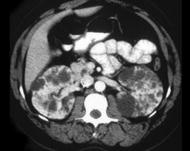

问题 女,35岁,无特殊临床表现,请根据CT图像,选择最可能诊断 ( )

选项 A、囊性肾癌 B、单纯性肾囊肿 C、多发性肾囊肿 D、复杂性肾囊肿 E、多囊肾

答案 E